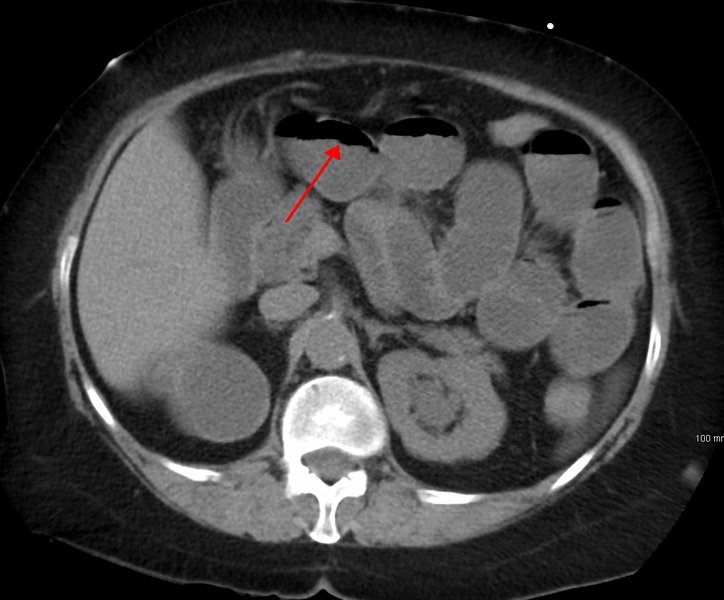

What is shown in the image?

CT scan demonstrating features of small bowel obstruction.